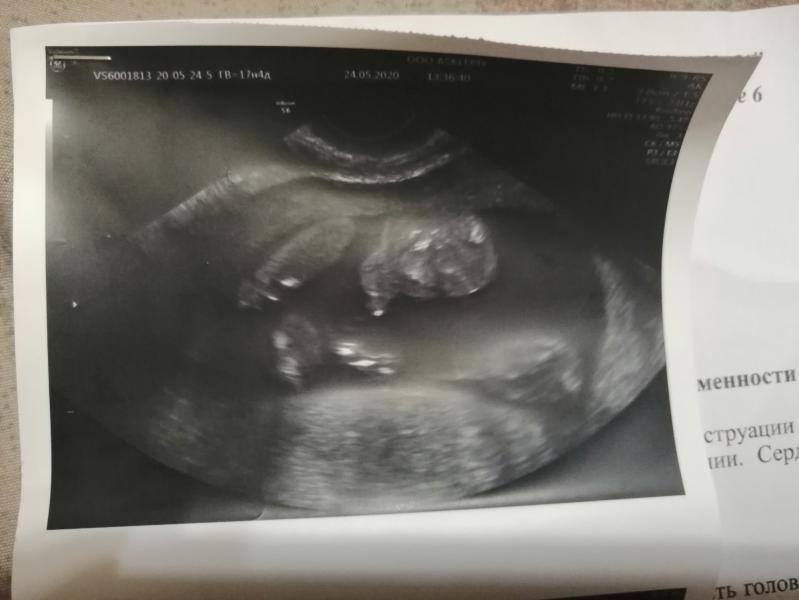

На узи сказали мальчик.. Сказал, давай сделаю фотку на память.. Все пытаюсь понять, где что.. Ну не сверху же это такие огромные... Ну и не могут быть так ноги раздвинуты... Или он просто так близко придвинул.. Не пойму.. Ну все равно слишком большое расстояние между ног.. Подскажите, пожалуйста, кто понимает...

Не понятно даже 🤭